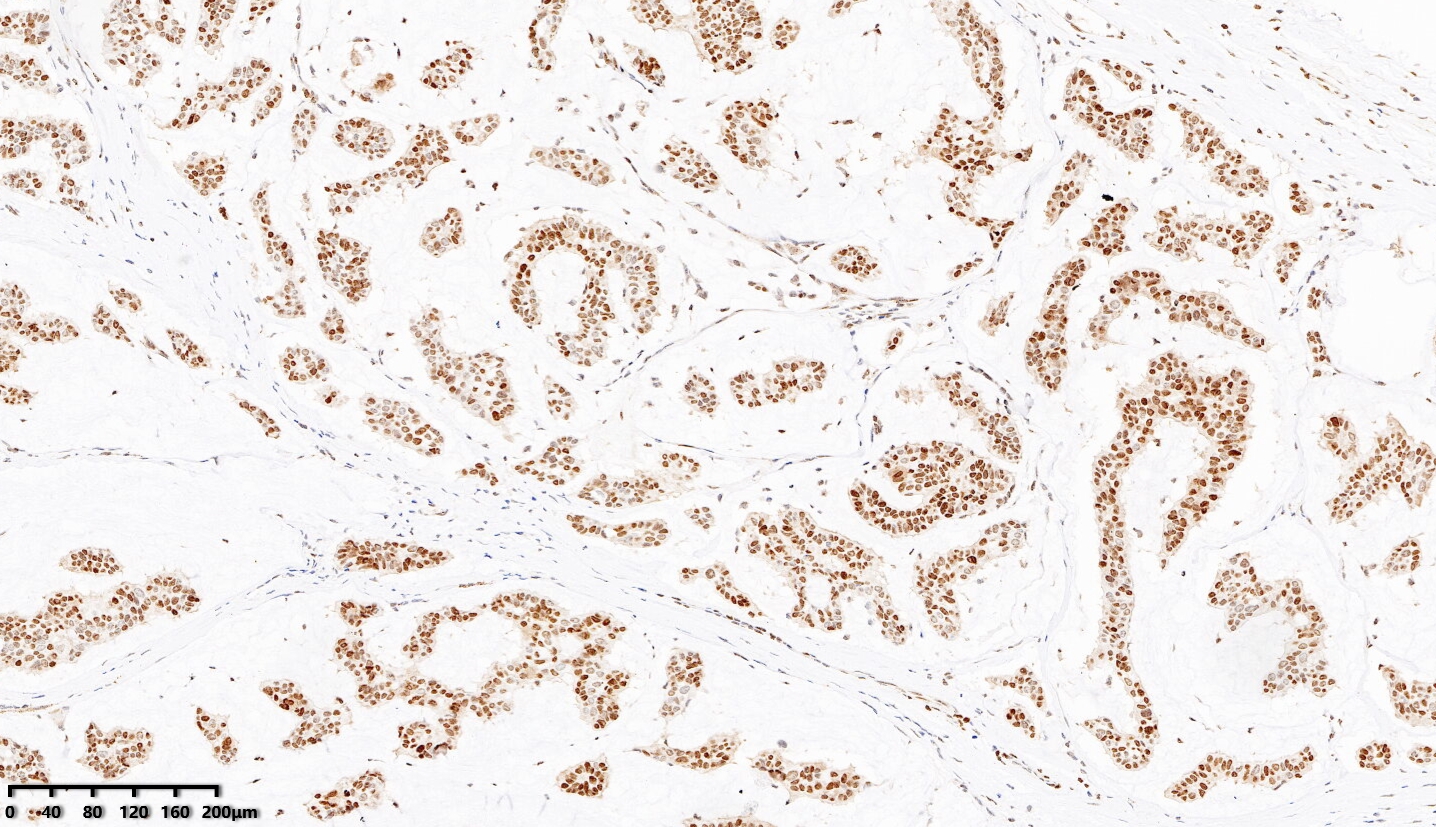

单克隆兔抗人BRCA1

| EPR19433 | 细胞浆/细胞核 | 乳腺癌 | 高PH热修复 |

乳腺癌,BRCA1染色,DAB显色